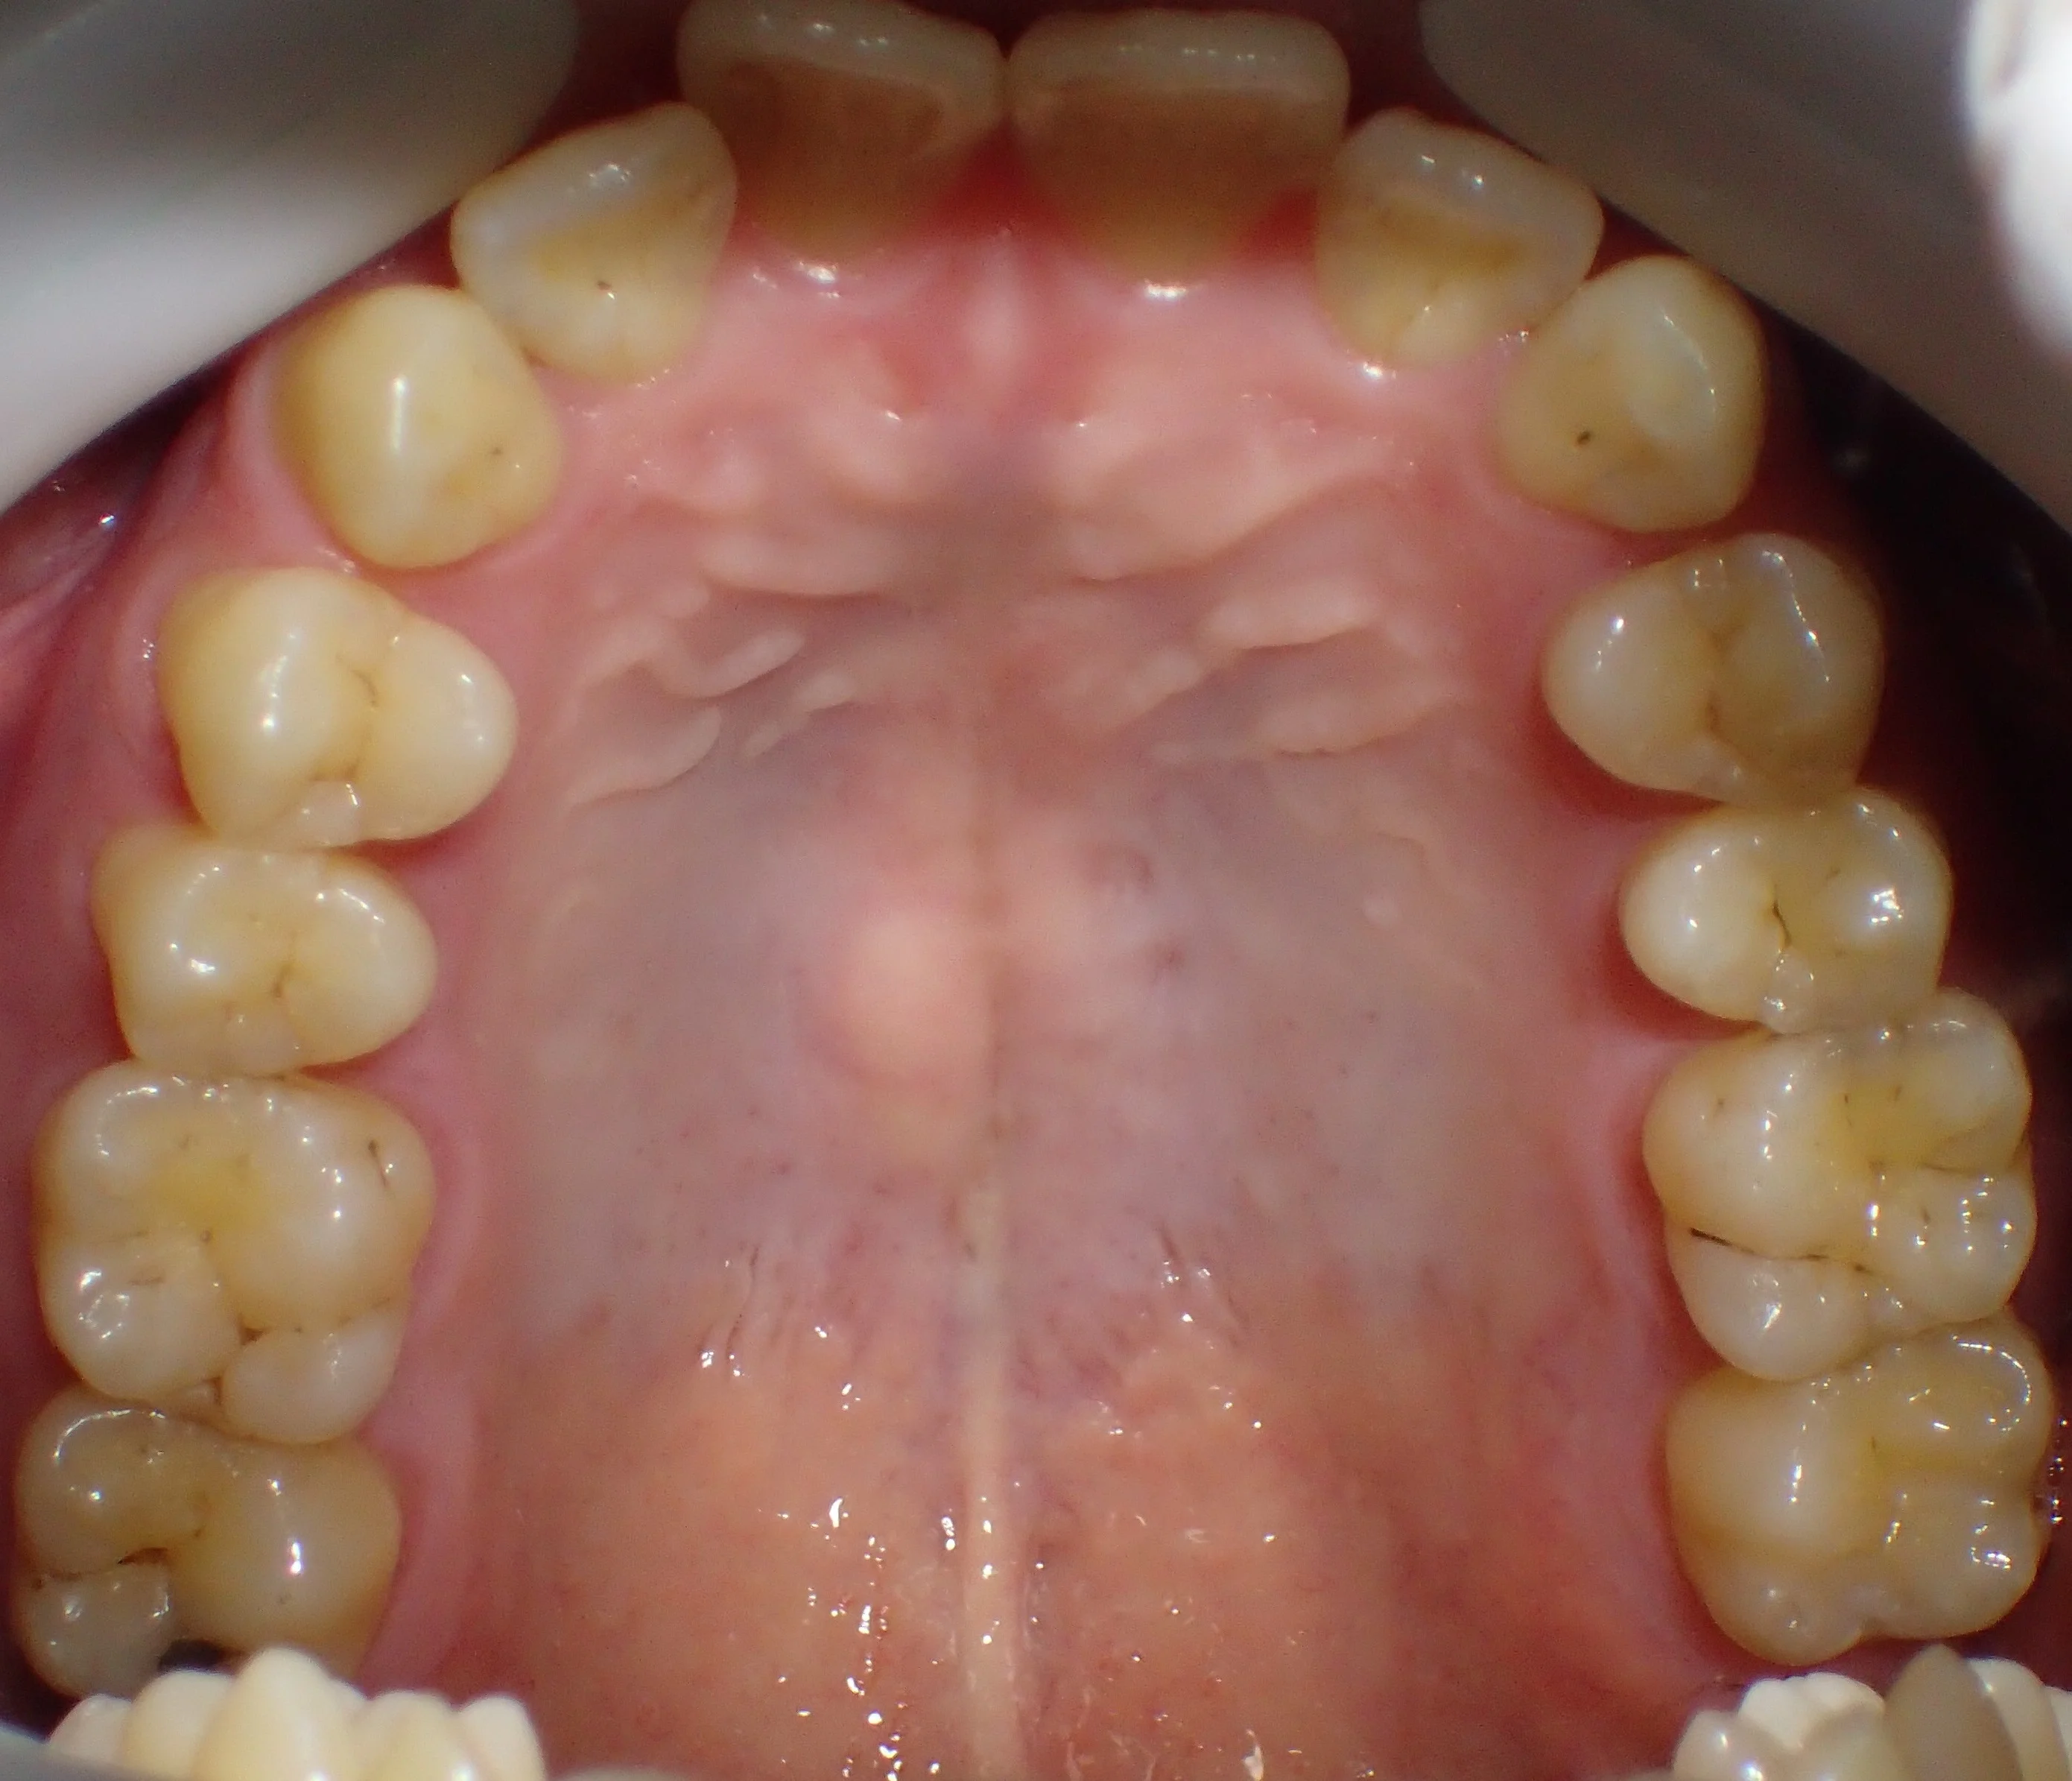

まだ坂寄歯科医院には全顎的にダイレクトボンディングで治療した症例がありませんので、前の医院にて治療を完了された方の写真を載せたいと思います。

どこを治療したかわかりますか?

答えは下の方に書いておきますので、スクロールしてください。

治療した箇所は、

・右上4,5,6

・左上4,5,6

・右下5,6

・左下5

でした!

治療した部位は全て元々詰めていたメタルインレーが再び虫歯になってしまった状態でした。

幸いあまり大きくは削られてはいなかったので、全てをダイレクトボンディングで治療することが出来ました。